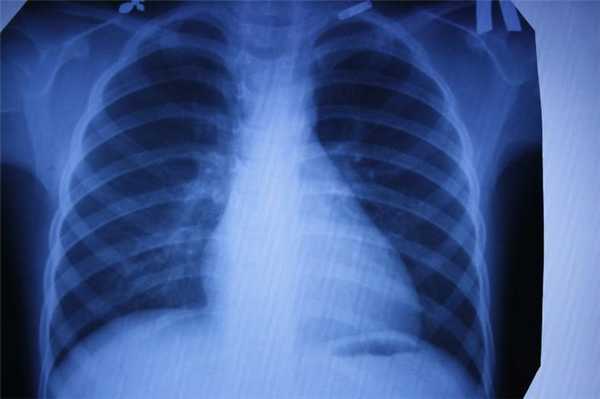

Флюорография

Ещё один тип обследования, которому регулярно все жители нашей страны. Флюорографию “изобрели” почти сто лет назад. Это своего рода ускоренная рентгенография. Учёные предложили фотографировать экран с изображением, полученным при рентгенографии. Это позволило сделать процедуру более быстрой и массовой. Скрининг-тесты начали делать всем, чтобы выявлять скрыто протекающий туберкулёз лёгких.

Главный плюс процедуры — быстрота, главный минус — качество изображения. Пациент также получает дозу облучения, а врач довольно размытую картинку, поэтому флюорографию рекомендуется дополнять анкетированием и лабораторными тестами на наличие туберкулёза.

Каждый метод дает разную информацию об исследуемых органах. Если говорить в целом, то КТ идеально «видит» легкие, и превосходит все другие методы в выявлении патологии дыхательной системы: и МРТ и рентген и флюорографию.

Для выявления патологии легких также назначают рентген и флюорографию…

Если речь идет о профилактическом осмотре, ежегодной диспансеризации, и у человека нет никаких жалоб - классическое рентгеновское исследование, которое дает меньшую, чем КТ лучевую нагрузку, можно считать достаточным. Но если пациент находится в группе риска по развитию рака легких (например, это курильщик с серьёзным стажем), лучше сразу сделать более информативную КТ. Андрей Дмитриевич Каприн, главный онколог России, рассказывает, что благодаря огромному количеству КТ- исследований легких, которые были сделаны за время пандемии, удавалось выявлять рак легких на самых ранних стадиях и множество других, не связанных с COVID-19 патологий. Низкодозовая КТ - лучший метод скрининга рака легких, она позволяет увидеть зарождающийся опухолевый процесс размером 2-3 мм и самые минимальные изменения, которые рентген может и пропустить.

- воспаление легких;

С помощью компьютерной томографии в медицинских центрах СПб проводят скрининг рака легких у курильщиков. Такая томография позволяет выявить в 2 раза больше опухолей на ранней стадии. Простая флюорография (на базе рентгена) рак легких не показывает, поскольку плоскостное изображение не видит маленькие очаги опухоли, а вот на КТ можно визуализировать новообразование до 1 мм величиной.